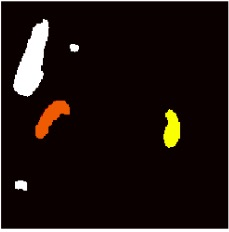

This work presents a novel framework CISFA (Contrastive Image synthesis and Self-supervised Feature Adaptation)that builds on image domain translation and unsupervised feature adaptation for cross-modality biomedical image segmentation. Different from existing works, we use a one-sided generative model and add a weighted patch-wise contrastive loss between sampled patches of the input image and the corresponding synthetic image, which serves as shape constraints. Moreover, we notice that the generated images and input images share similar structural information but are in different modalities. As such, we enforce contrastive losses on the generated images and the input images to train the encoder of a segmentation model to minimize the discrepancy between paired images in the learned embedding space. Compared with existing works that rely on adversarial learning for feature adaptation, such a method enables the encoder to learn domain-independent features in a more explicit way. We extensively evaluate our methods on segmentation tasks containing CT and MRI images for abdominal cavities and whole hearts. Experimental results show that the proposed framework not only outputs synthetic images with less distortion of organ shapes, but also outperforms state-of-the-art domain adaptation methods by a large margin.